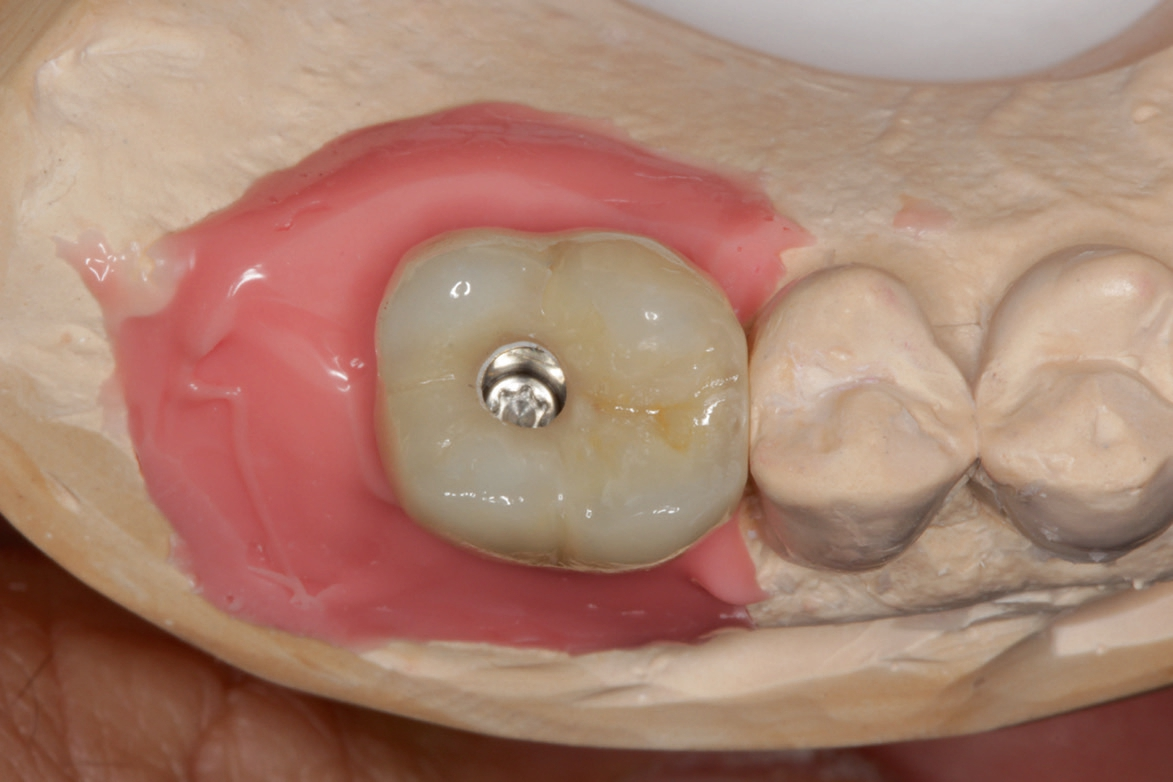

Die Übertragung der Implantatposition ins zahntechnische Laboratorium wird mittels offener Abformung mit individuellem Löffel und einem stabilen Polyäthermaterial vorgenommen. Die achsgerechte Position des Implantates ermöglichte die Anfertigung einer transocclusal verschraubten, verblendeten Zirkonoxidkrone auf einer Klebebasis. Die Besonderheit der Konstruktion ist dabei, dass das Metall der Klebebasis bei der fertigen Konstruktion komplett von Zirkon umschlossen ist. Dies erfordert eine hohe technische Präzision und eine spezielle „Verklebehilfe“ im Labor. Zur ersten Einprobe der Krone beim Patienten befestigen wir die Krone zunächst nur provisorisch auf der Klebebasis. Dies stellt sicher, dass sie bei eventuell notwendigen Korrekturen leicht gelöst und erneut gebrannt werden kann. Ist die Krone in Farbe und Form fertig gestellt, so muss sichergestellt sein, dass die endgültige Verklebung exakt in der gleichen Position auf der Klebebasis erfolgt, wie die zuvor einprobierte. Dafür fertigen wir einen Kunststoffschlüssel.

Vor Eingliederung der Krone wird die Hygienefähigkeit geprüft und sichergestellt, dass zukünftig in Okklusion und Artikulation keine traumatischen Kräfte auf die Restauration wirken. Nach Anziehen des erforderlichen Drehmoments wird der Schraubenkanal mit Teflonband gefüllt und ein okklusaler Verschluss mit Komposit vorgenommen.